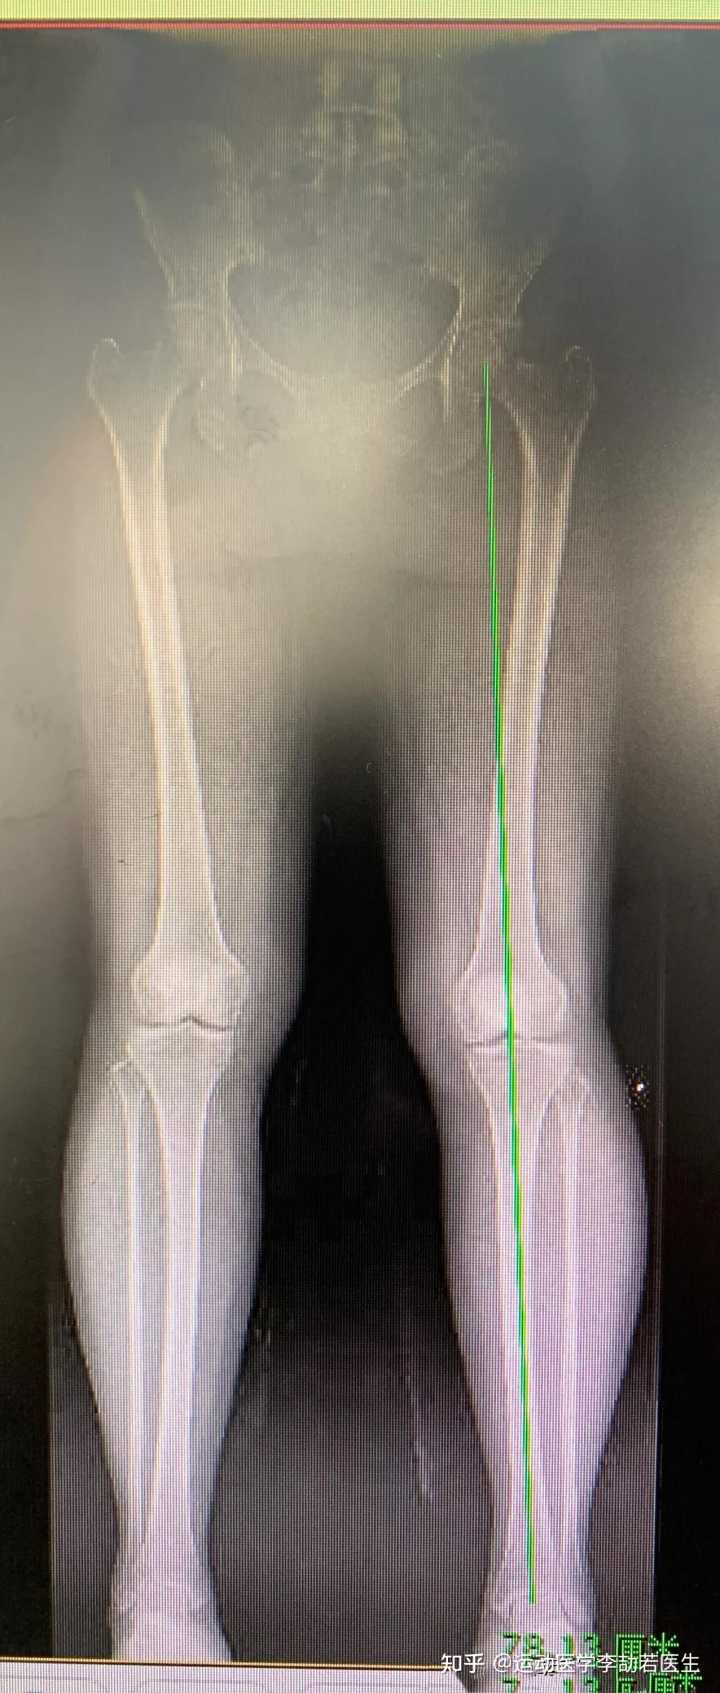

骨关节炎有哪些好的治疗方法?

从椅子上站起来,膝盖疼痛,是跑步膝还是骨关节炎,哪个更严重?